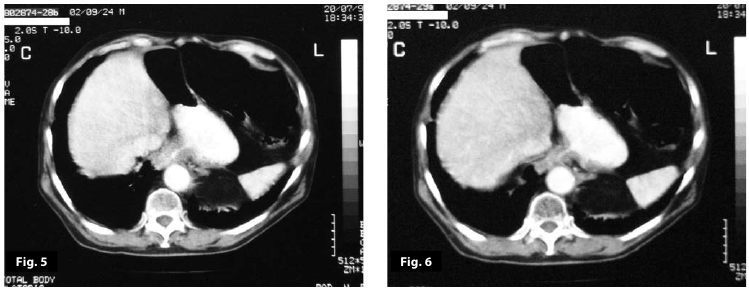

Figure5

Figure6

Figure5-6